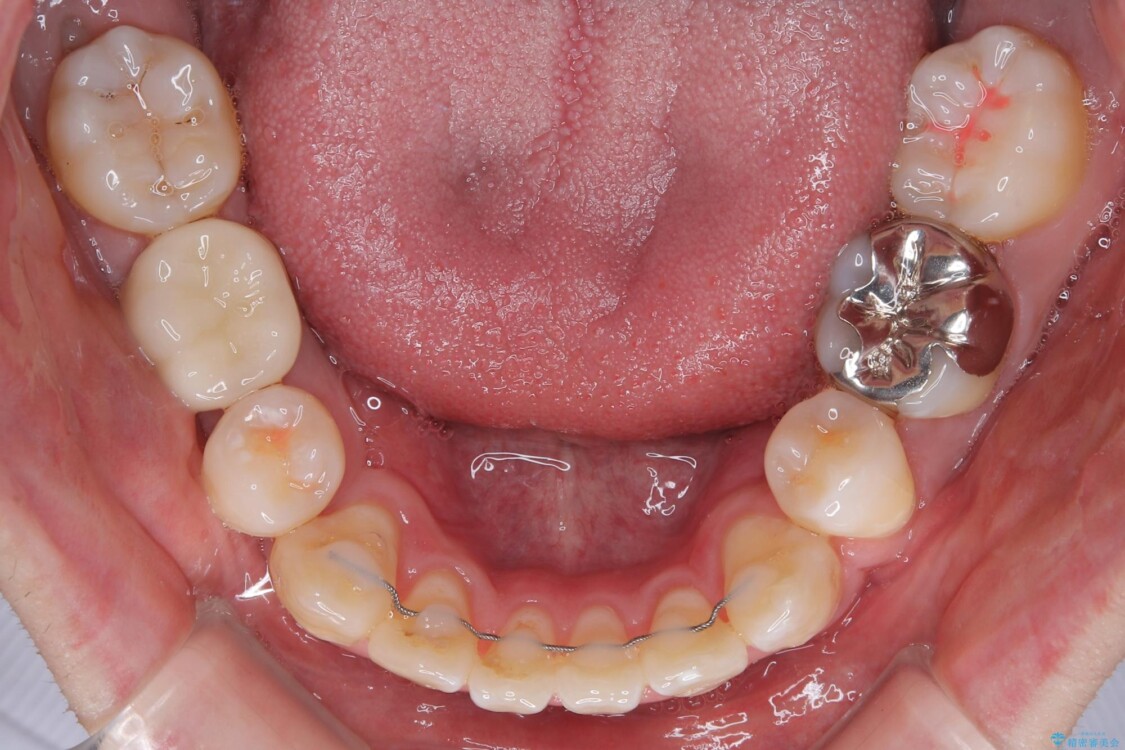

治療途中

• 口元の突出感を改善!目立ちにくいワイヤー矯正で自信を持てる自然な横顔に 治療途中画像

精密検査の結果、上下左右の小臼歯4本を抜歯し、そのスペースに前歯を後方へ移動させる矯正治療をご提案しました。